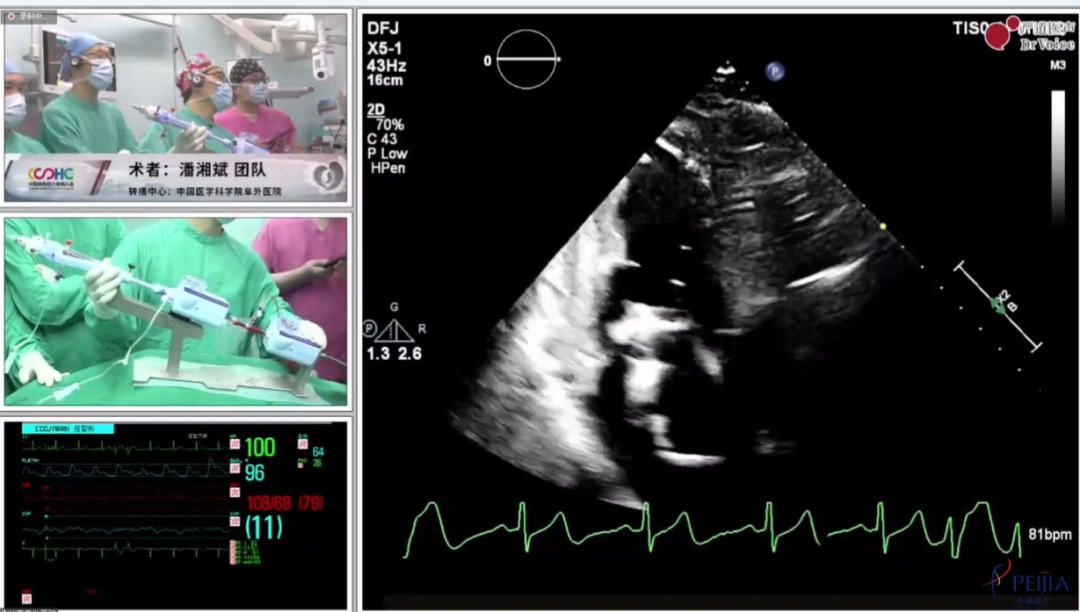

弹道垂直于二尖瓣平面

将MitraClip™推进至左心室,双臂朝向垂直于瓣叶边缘的长轴